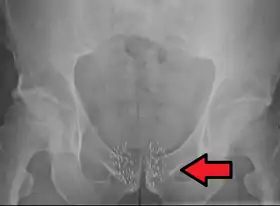

Arrow points to brachytherapy beads used to treat prostate cancer.

Brachytherapy to treat prostate cancer can be given either as permanent LDR seed implantation or as temporary HDR brachytherapy.[1]:Ch. 20[33][34]

Permanent seed implantation is suitable for patients with a localised tumour and good prognosis[33][35][36][37] and has been shown to be a highly effective treatment to prevent the cancer from returning.[35][38] The survival rate is similar to that found with EBRT or surgery (radical prostatectomy), but with fewer side effects such as impotence and incontinence.[39] The procedure can be completed quickly and patients are usually able to go home on the same day of treatment and return to normal activities after one to two days.[6] Permanent seed implantation is often a less invasive treatment option compared to the surgical removal of the prostate.[6]

Permanent brachytherapy, also known as seed implantation, involves placing small LDR radioactive seeds or pellets (about the size of a grain of rice) in the tumour or treatment site and leaving them there permanently to gradually decay. Over a period of weeks or months, the level of radiation emitted by the sources will decline to almost zero. The inactive seeds then remain in the treatment site with no lasting effect.[76] Permanent brachytherapy is most commonly used in the treatment of prostate cancer.[82]